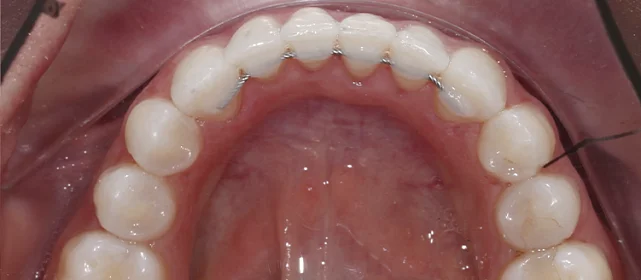

Зубы выровнены, смыкание нормализовано. Установлены несъёмные ретейнеры на обе челюсти, изготовлены ретенционные капы. Пациентка предварительно проконсультирована ортопедом онлайн.

Решение: Поставили элайнеры 3D Smile на обе челюсти. Лечение заняло 4 года и потребовало нескольких последовательных этапов коррекции. Капы менялись каждые 1–2 недели, на контрольных визитах отслеживали прогресс и выдавали новые наборы. Зубы встали в правильное положение, смыкание нормализовалось. Зафиксировали ретейнеры на обе челюсти, изготовили ретенционные капы. Пациентка прошла онлайн-консультацию с ортопедом для оценки дальнейших шагов.

Лечение потребовало нескольких последовательных этапов — каждый дозаказ кап уточнял положение зубов, которые не полностью отреагировали на предыдущий курс. Элайнеры 3D Smile позволяют работать поэтапно, корректируя план по ходу. Результат получен, ретейнеры зафиксированы. Рекомендовала пациентке консультацию ортопеда для оценки состояния зубов после лечения